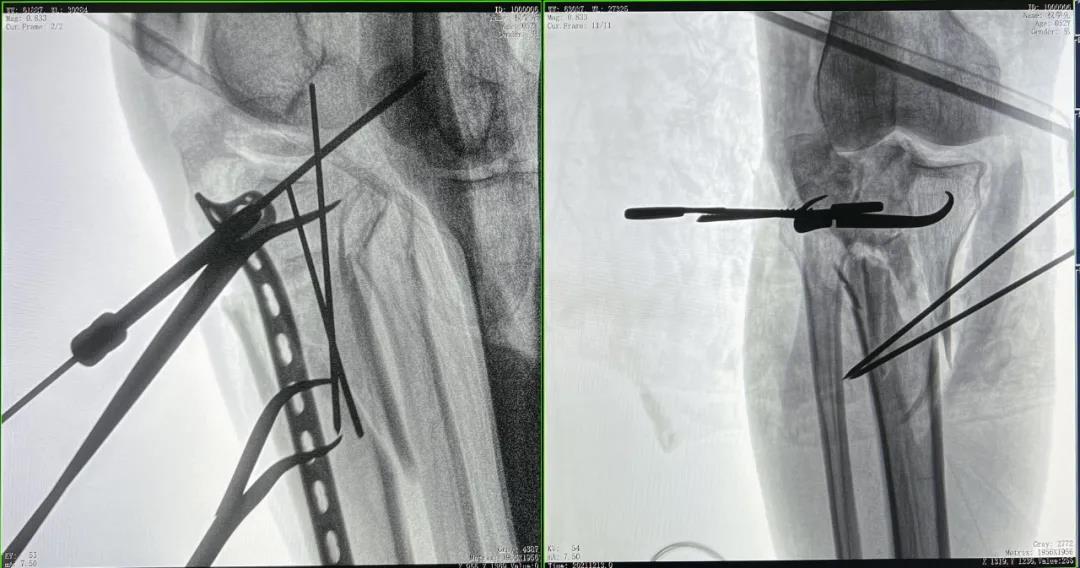

患者2:男性,52歲,脛骨骨折切開復位鋼板內固定術

術前CT三維重建影像可見脛骨平臺處粉碎性骨折

優質的術中影像輔助螺釘準確植入